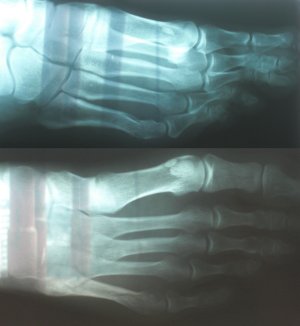

Снимок в реале не намного лучше, интересует место отмеченное кругом. Нога правая, верхнее фото - проекция с наружной стороны, нижнее фото - проекция сверху. Диагноз был поставлен перелом 5й плюсневой кости (без подробностей), впринципе по снимку это видно. поэтому и написал в этой теме. Подскажите тогда по выбору иммобилизации (и нужна ли она вообще) и ее срокам при таком повреждении.По такому плохому фото диагноз не ставят даже по снимку. Диагноз ставит врач при личном обращении пациента.

В данном случае какую иммобилизацию Вы бы рекомендовали и на какой срок? Работа связана с вождением автомобиля, т.е. давление на педали (нога правая). Когда можно приступать? После перелома полдня ездил нормально, до травмпункта доехал сам.Что то похожее на спиралевидный дистальный перелом.

35 лет. Рост 185. Вес 75. Как любитель занимаюсь активными видами спорта (виндсерфинг, сноуборд итд.). Перелом 17 марта от падения тяжелого предмета на стопу. Снимок сделан примерно через 3 часа.Я ведь про вас ничего не знаю, сколько лет,Ю ваша физическая форма, конституционный тип, время перелома...